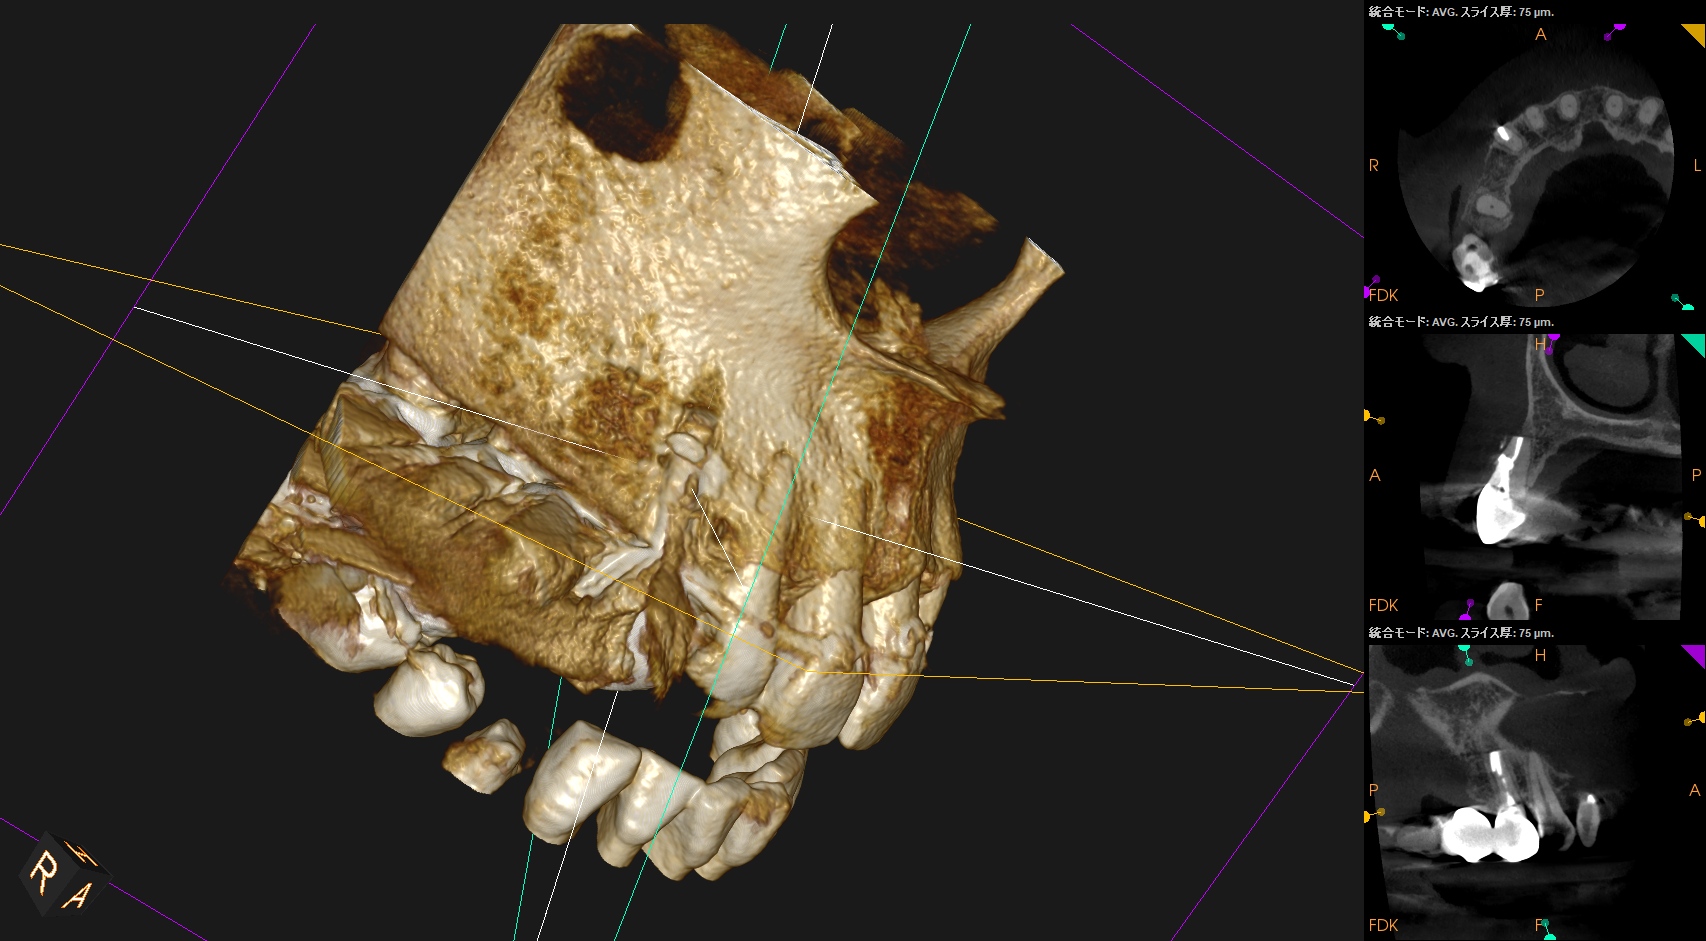

PA, CBCTを撮影した。

しょっぱい逆根管形成になったが主根管は確保されたので縫合して終了した。

#6 Invasive Cervical Root Resorption Repair, Apicoectomy 4M recall(2026.2.13)

根切した部分にはだいぶ骨が添加されているし、外部吸収も進展していないようだ。